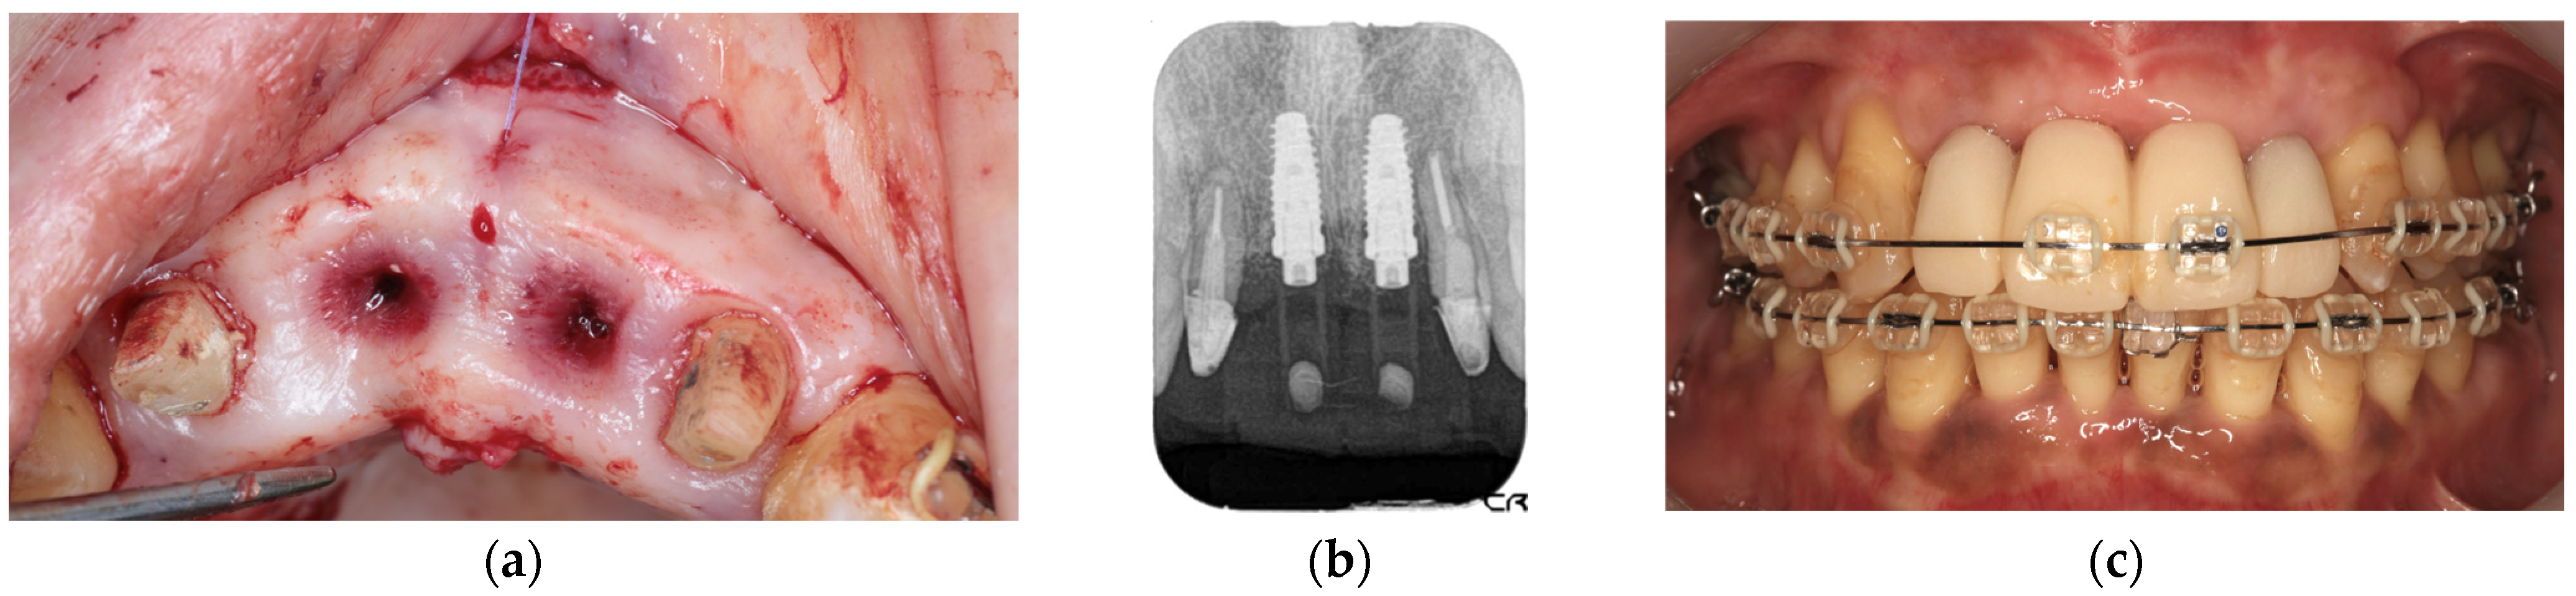

The second-stage implant exposure procedure was conducted in March 2017. Subsequently, a connective tissue graft was applied to enhance the soft tissue volume and improve aesthetic outcomes (Figure 9a). Provisional restorations were placed (Figure 9b), and orthodontic treatment was initiated (Figure 9c). The orthodontic treatment was completed in February 2018. Although the implant on the left side was in close proximity to the adjacent tooth, no clinical issues were observed around the implant or in the remaining teeth immediately after placement or during the provisional restoration period. Therefore, porcelain-fused-to-zirconia restorations were installed in the month (Panavia; Kuraray Noritake Dental Inc., Niigata, Japan) (Figure 10). Due to the low bone support of the maxillary bilateral lateral incisors and potential complications, screw retention was preferable to allow prosthetic device replacement. However, the structural complexity of the connection with the natural teeth makes screw retention difficult; therefore, the superstructure was cemented. Although provisional cementation would have been ideal for potential reprosthetics, luting cement was used to prevent intrusion of natural teeth. The patient’s oral aesthetics showed notable enhancement since the initial consultation, as depicted in Figure 11.

Figure 9. Intraoral photograph during connective tissue grafting (a), dental radiograph after provisional restoration placement (b), and orthodontic treatment (c).

Diagnostics 15 00765 g009